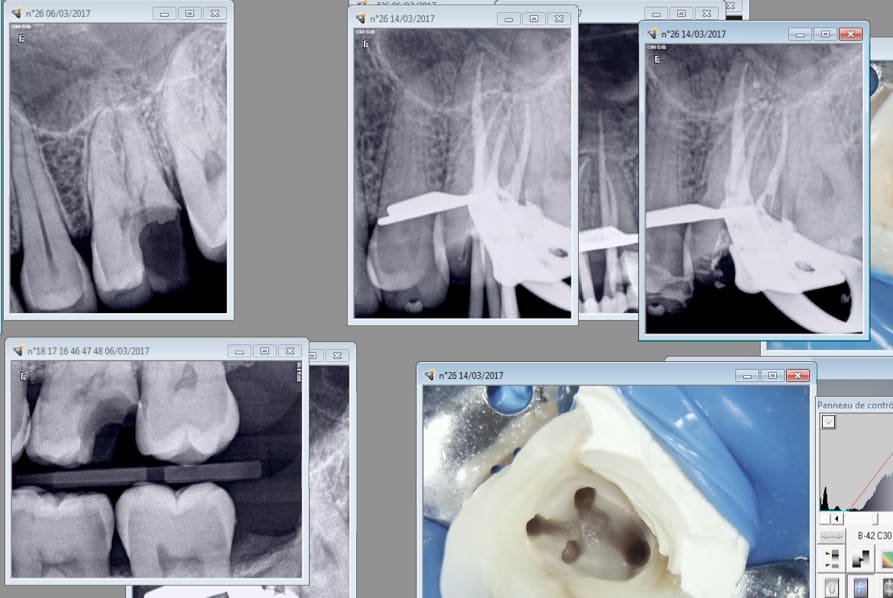

Mes endos masters commencent à merder donc j'ai utilisé le joypex 5 acheté 80 euros sur Ebay.

Résultat : 20 mn l'endo sur cette 26.

Ces 2 là 1h de RDV expédiées en 25 mn. -) Malheureusement j'avais un doublon de RDV. Sinon ca aurait été passé au taille crayon dans la foulée. -)

J' alterne le localisateur sur l'entran ( S1) et WDW connect ( réciproc R25 blue)

J'aime pas finir des soins que je n'ai pas commencé. A votre avis perfo distale ou carie pré existante ? -)

Le patient se plaignait depuis longtemps d'une douleur niveau 26 27 avec pèche ca m'étonnerait que 16 ( je pense intacte au début) en soit la cause car il y a une image sur la racine mésiale de 17. Fracturée ou MV2 non traité ? Bizarre bizarre.

Ah oui le canal palatin était vivant.